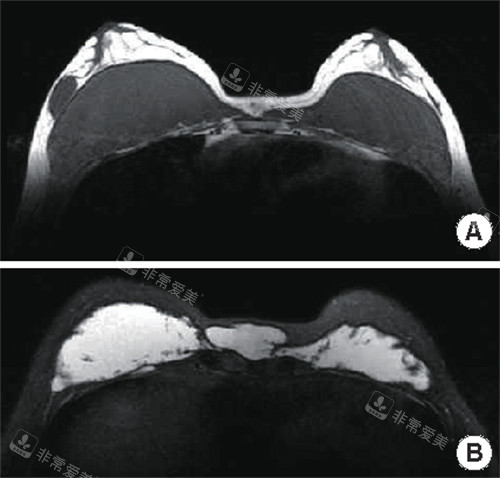

他指着术前的影像,上面布满星星点点的白色异物影,又切换到术后的影像。

对比之强烈,让我瞬间屏住了呼吸——原先大片的白色异物影基本消失了,只剩下极少数几个细微的、几乎可以忽略不计的小点。

院长用笔圈出那几个小点说:“这是紧贴重要神经和血管的极微量残留,强行剥离风险太大,会得不偿失。

它们已经被隔离,不会再有活性,将来也绝不会影响健康。

目前的取出率,根据影像评估,在98%左右,这是一个非常理想的结果。”

“98%……”我重复着这个数字,看着那两张天壤之别的片子,一直压在心头的那块巨石,轰然落地。

那一刻的感觉,不是单纯的喜悦,而是一种深切的、劫后余生般的解脱与安心。

那张显示残留极少的术后片子,不仅是一张医学影像,更是我重获安心与自信的证明。